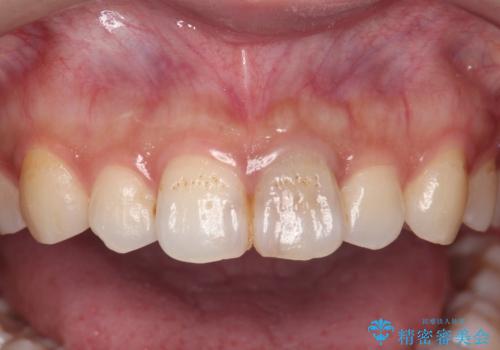

長期的な予後を見通すことが難しかったので、亀裂のある前歯の抜去を行いブリッジで審美性・機能性の回復を行いました。

- 36.3万円(仮歯・ジルコニアクラウン×3)費用は治療当時の料金となります